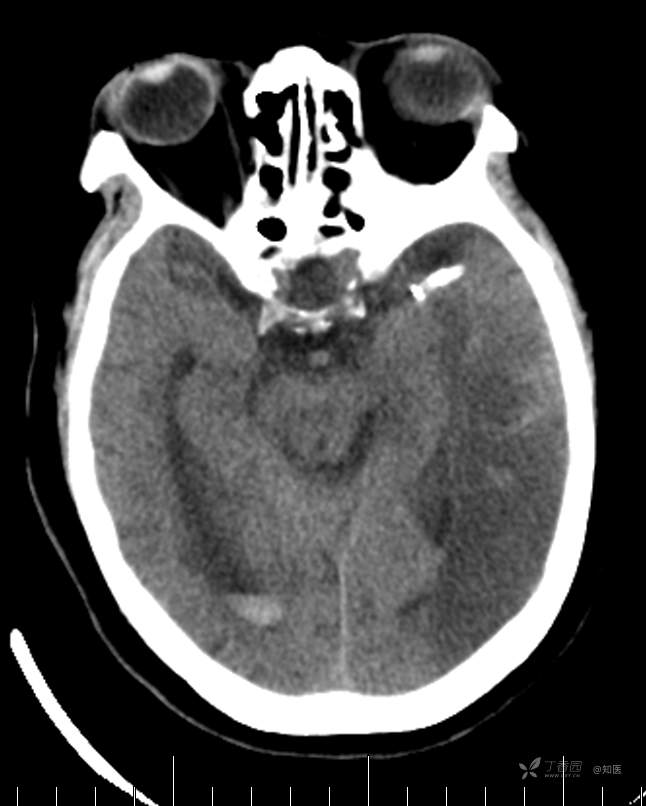

辅助检查:头颅MRI+DWI(2021.04.21 西安市红会医院):1.桥脑、双侧额顶叶、半卵圆中心、侧脑室旁及基底节区多发缺血灶、腔梗灶,部分软化灶。脑白质脱髓鞘改变,脑萎缩。DWI未见确切异常增高信号。

4-22日查房患者呈昏睡状,混合性失语,右侧肢体肌力障碍较入院时加重,胃肠减压引流物为深黄绿色液体,量约150ml。查体:GCS 9分(睁眼反应 3分+语言 1分+运动 5分),NHISS评分23分(意识水平 2分+提问 2分+指令 1分+凝视 2分+面瘫2+左上肢 1分+右上肢4分+左下肢 2分+右下肢4分+语言 3分),昏睡状,查体欠合作,混合性失语,粗测智能查体不配合。双眼闭目紧,双侧球结膜水肿,双侧瞳孔等大等圆,直径约4.0mm,对光反射灵敏,眼球无自主运动,无眼震,右侧鼻唇沟浅,口角向左歪斜。咽部查体不配合。转颈、耸肩查体不配合。伸舌不配合。右上肢肌力1级,右下肢肌力2级,左上肢肌力3级,左下肢肌力4级,四肢肌张力减低。四肢深浅感觉及共济运动查体不配合。右侧巴氏征阳性,左侧巴氏征阴性。颈抵抗。双侧布氏征及克氏征均阴性。辅助检查:头颅+胸部CT:与前片(2021-4-21 13:57)对比,现片示:1、环池、桥前池及大脑镰后部及小脑幕高密度影,考虑出血,较前新发。2、额颞顶叶高低混杂密度影,考虑梗塞伴造影剂残留;左侧大脑中动脉走行区致密影,系术后改变;请结合临床。3、多发腔梗,脑白质脱髓鞘,脑萎缩。4、双肺间质性改变,双肺下叶纤维索条,双侧胸腔微少量积液征象,双侧胸膜增厚。5、主动脉及冠状动脉管壁多发钙化斑块。三线主任医师、二线主治医师查房后示:根据患者病史、体征及辅助检查,目前诊断:1.脑梗死出血转化;2.左侧大脑中动脉次全闭塞;3.左侧大脑中动脉支架植入术后;4.高血压2级(很高危);5.2型糖尿病;6.应激性溃疡伴出血。目前病情及治疗上需注意以下问题:1.患者出血转化,增加脱水剂剂量,调整为20%甘露醇 125ml 每8小时一次、甘油果糖 250ml 每12小时一次,同时结合患者球结膜水肿,白蛋白正常低值,今日给予补充人血白蛋白10g,注意监测电解质等变化。2.患者为蛛网膜下腔出血,给予泵入尼莫地平预防脑血管痉挛。3.患者左侧大脑半球见大片脑白质脱髓鞘,考虑脑白质营养不良,给予维生素B1、维生素B12、维生素C、维生素B6及依达拉奉改善微血管通透性;4.患者出现应激性溃疡伴出血,今日暂禁食,给予泮托拉唑抑酸及肠外营养补充,密切观察消化道出血情况,根据病情变化调整抑酸药物剂量及频次;5.患者卧床,今晨见明显痰多,给予化痰等对症处理,监测血常规及脓毒症2项指标。6.向家属再次告知病情,因患者高龄、既往高血压及糖尿病病史,此次治疗出现出血转化,存在意识障碍加深、病情加重可能。7.密切观察神经系统体征变化。遵嘱执行。